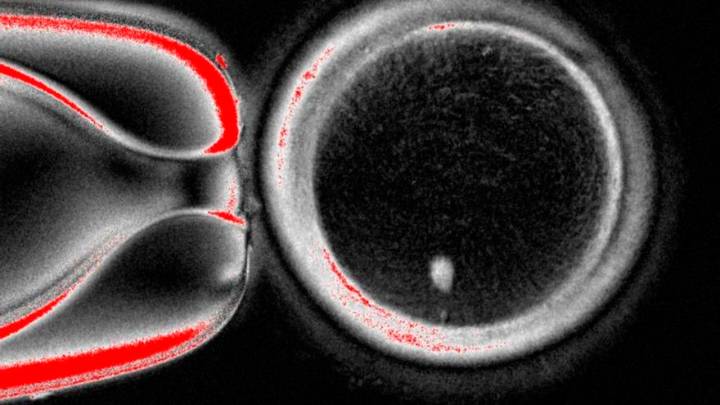

París, 01 de octubre del 2025.- Científicos anunciaron el martes que lograron por primera vez convertir células de la piel humana en óvulos y fertilizarlos con esperma en laboratorio, un avance que podría hacer posible algún día que mujeres infértiles tengan hijos.

Este nuevo enfoque en el campo de la gametogénesis in vitro permitiría que mujeres mayores o que no producen óvulos por otras razones puedan reproducirse genéticamente, explicó a Afp Paula Amato, coautora del estudio.